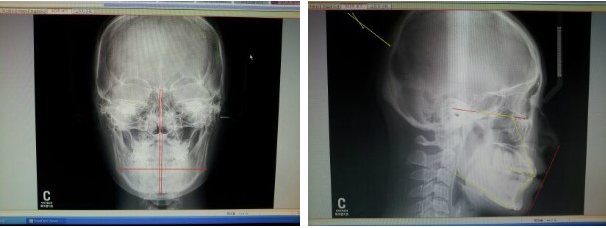

왼쪽 정면해골사진은 콧대와 턱끝까지 수직선을 긋고 좌우대칭을 보는중인데

전 뼈구조상으로는 좌우대칭이 잘 맞는 편이래요

그런데 정면사진에 턱이 한쪽이 더 큰것은 아마도 어금니가 빠진후 한쪽으로만 씹는 습관때문에 근육이 커진것같다고 하셧어요

오른쪽 측면해골사진은 코끝과 턱끝을 선으로 이엇을때 입이 돌출되어진 정도를 보는거에요

선에 입술이 딱 닿아잇죠

심한분들은 선밖으로 나오기도 하는데 다행히 전 콧대가 높은덕에 ㅋㅋ 측면으로 보면 또 입이 덜 나와보여요